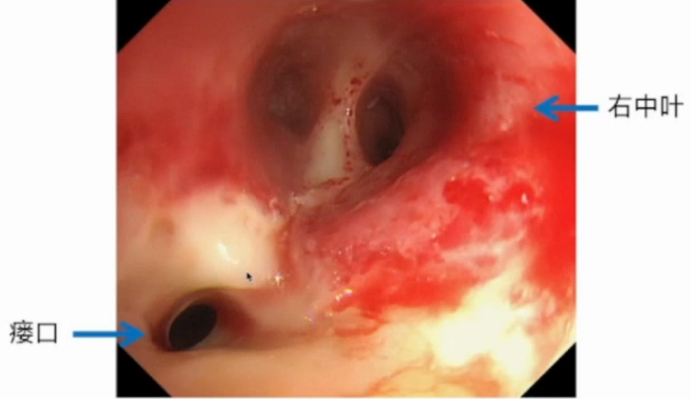

术后第23天,气管镜检查于右肺中叶开口侧壁发现瘘口(图4),考虑出现支气管胸膜瘘。术后第31天,复查胸部CT可见肺部膨胀不佳(图5)

4  气管镜下发现瘘口